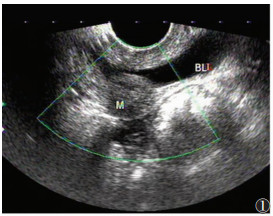

超声共发现病灶区101个(图 1~4),敏感度79.5%,超声诊断与手术结果对照见表 1。经阴道超声诊断的最低敏感度(64.4%)和准确率(79.7%)在阴道,最高敏感度(94.6%)和准确率(97.5%)在直肠子宫陷凹。

| 图 1 34岁,膀胱病灶,表现为尿路刺激征,疑泌尿系感染,超声示膀胱后壁低回声团,边界欠清,回声欠均,血流信号不明显(BL:膀胱;M:病灶) |

DIE病灶超声表现:呈结节状、片状或不规则形,边界欠清、不规整。可与周边组织粘连;多为低回声区,偶为等、高回声区,内部回声不均匀,可见细小无回声区,透声欠佳,CDFI可见部分病灶散在短杆或点状的穿枝型血流病灶(17/101,16.8%)。

各部位DIE病灶的诊断要点:①宫骶韧带表现为宫颈下段两侧旁结节样或条索样低不规则回声区;宫旁组织、子宫浆膜面病灶呈不规则片状或斑块状低回声,注意与子宫浆膜下肌瘤鉴别。②超声直接在输尿管周围或内部发现明显病灶较困难,伴输尿管扩张的DIE可增加诊断率,本研究中2例均因输尿管扩张而诊断,但需注意排除,如结石、先天性狭窄等梗阻因素。③膀胱病灶由于尿液透声窗衬托,诊断敏感度较高,病灶常见于后壁,呈低回声结节,可局限于膀胱浆膜面,超声可评估病变的侵犯深度。④本研究中经阴道超声对直肠子宫陷凹病灶诊断敏感度和准确率最高,与文献[8]报道一致,直肠子宫陷凹粘连封闭为DIE显著特征,也可表现为不规则低回声区,与子宫后壁分界不清。⑤阴道、直肠、阴道直肠隔DIE病灶常经妇检首先发现,经阴道超声诊断敏感度偏低,表现为局部不规则低回声区,探头触痛,检查中注意分清三者毗邻结构关系,精确定位病灶侵犯部位。直肠病灶常与宫颈后区病变粘连,造成直肠子宫陷凹闭锁。⑥DIE超声表现虽有一定的特征性,但也需与盆腔脏器恶性肿瘤鉴别。DIE病灶对腹膜脏器浸润是从外(浆膜层)向内(肌层),而肿瘤对肠壁脏器的浸润则是自内(黏膜层)向外(浆膜层)。直肠子宫陷凹病灶需与肿瘤的腹膜转移灶鉴别,两者表现相似,但肿瘤结节的外形较规则,CDFI血流信号丰富,而DIE形态多呈不规则斑片状,CDFI血流信号稀少;且转移瘤常伴腹腔积液,结合其他辅助检查可发现相关原发肿瘤,有助于确诊。

各部位DIE病灶的诊断要点:①宫骶韧带表现为宫颈下段两侧旁结节样或条索样低不规则回声区;宫旁组织、子宫浆膜面病灶呈不规则片状或斑块状低回声,注意与子宫浆膜下肌瘤鉴别。②超声直接在输尿管周围或内部发现明显病灶较困难,伴输尿管扩张的DIE可增加诊断率,本研究中2例均因输尿管扩张而诊断,但需注意排除,如结石、先天性狭窄等梗阻因素。③膀胱病灶由于尿液透声窗衬托,诊断敏感度较高,病灶常见于后壁,呈低回声结节,可局限于膀胱浆膜面,超声可评估病变的侵犯深度。④本研究中经阴道超声对直肠子宫陷凹病灶诊断敏感度和准确率最高,与文献[8]报道一致,直肠子宫陷凹粘连封闭为DIE显著特征,也可表现为不规则低回声区,与子宫后壁分界不清。⑤阴道、直肠、阴道直肠隔DIE病灶常经妇检首先发现,经阴道超声诊断敏感度偏低,表现为局部不规则低回声区,探头触痛,检查中注意分清三者毗邻结构关系,精确定位病灶侵犯部位。直肠病灶常与宫颈后区病变粘连,造成直肠子宫陷凹闭锁。⑥DIE超声表现虽有一定的特征性,但也需与盆腔脏器恶性肿瘤鉴别。DIE病灶对腹膜脏器浸润是从外(浆膜层)向内(肌层),而肿瘤对肠壁脏器的浸润则是自内(黏膜层)向外(浆膜层)。直肠子宫陷凹病灶需与肿瘤的腹膜转移灶鉴别,两者表现相似,但肿瘤结节的外形较规则,CDFI血流信号丰富,而DIE形态多呈不规则斑片状,CDFI血流信号稀少;且转移瘤常伴腹腔积液,结合其他辅助检查可发现相关原发肿瘤,有助于确诊。